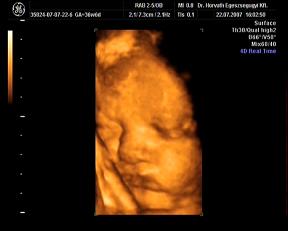

ma megvolt a -ha minden igaz- utolsó ultrahang. Nagyon jó volt, kisit furcsa érzés, hogy Ákossal már nem megyünk ilyenre...de nemsokára gyönyörködhetek benne állandóan 4D-ben-hanggal:D:D:D

Nagyon jól van, hála Istennek, csinált adoki flowmetriát is-az is rendben teljesen. A súlya 2870 gramm-ideális, a méretei a korának megfelelőek. A doki azt mondta, úy készüljek, hogy maximum két hétvégém van még az Urammal kettesben:D:D:D Nagyon várom már!!

Rakok náhény képet:

édes kis grimaszai vannak, nem? :oops: